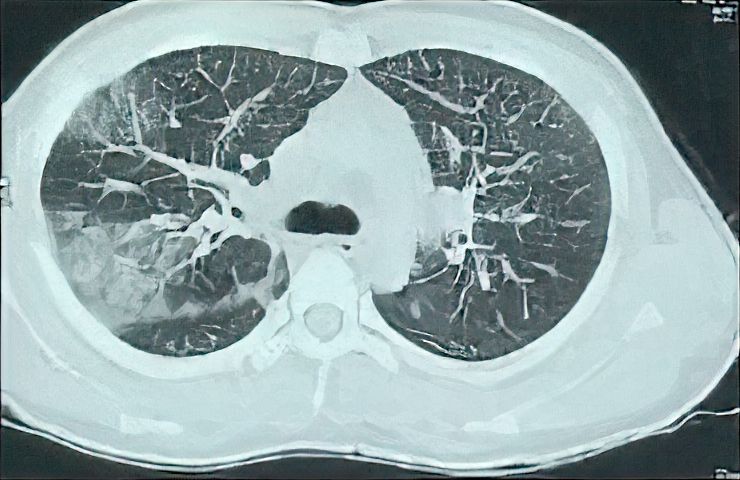

Figure 1. The Initial CT of the Patient Shows Interlobular Septal Thickening, Right Upper Lobe Consolidations and Ground Glass Opacity.

On examination, blood pressure was 120/80 mmHg, pulse rate 110/min, peripheral oxygen saturation (SpO2) 80% without oxygen, and respiratory rate 32/min. No abnormalities of the abdomen or central nervous system were observed. There were scattered crepitations in both infrascapular areas and the right inframammary area. High-resolution chest CT (HRCT) showed bilateral ground glass opacities, which were more obvious in the posterior segment of the right upper lobe and middle lobe in addition to the bilateral interlobular septal thickening (Figure 1).

Ground-glass opacity and interlobular septal thickening were observed in our case, which are common findings on chest CT in pulmonary strongyloidiasis. This CT observation shows that alveolar hemorrhage might be employed as a possible marker for the shift from asymptomatic to symptomatic condition (4). The number of larvae in the host of HS patients constantly increases. As a result, numerous larvae penetrate through the alveolar membranes, causing massive tissue damage in some cases. This is thought to be the cause of bacterial pneumonia and alveolar hemorrhage (10).